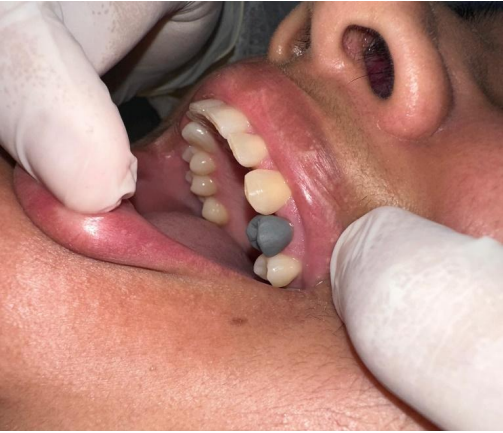

Paciente: E.B.S, sexo feminino, idade 34 anos, compareceu a clínica odontológica para início de tratamento reabilitador do elemento 24 (primeiro prémolar superior esquerdo, que havia sido submetido a um tratamento endodôntico, com necessidade de reforço do remanescente coronário e a confecção da coroa total protética fixa, para reestabelecer a função e estética.

1ª Sessão: Inicialmente foi realizado a desubturação parcial dos canais radiculares, mantendo o selamento apical com o comprimento mínimo para garantir o sucesso endodôntico. Em seguida, foi realizada a prova e ajuste do pino de fibra de vidro, o qual apresentou boa adaptação, dessa forma, foi feita a anatomização dos condultos e cimentado com cimento resinoso dual, considerando o protocolo adesivo adequado: condicionamento ácido, aplicação dos adesivos compatíveis e inserção do cimento nos canais, garantindo o preenchimento adequado e ausência de bolhas, após essa etapa, foi realizada a fotoativação e fotopolimerização completa, o núcleo coronário foi preenchido com resina composta para criar um remanescente anatômico que possibilitasse a confecção do preparo. Na sequência foi realizado o preparo para receber a coroa total, respeitando os princípios da retenção, resistência e espessura do material. Para a moldagem funcional a gengiva foi afastada com o fio retrator, e executada com silicona de condensação (pesada e leve), garantindo a cópia fiel dos limites cervicais. Posteriormente foi confecciada uma coroa provisória em resina composta, devidamente com a oclusão ajustada e protocolos de polimento, proporcionando conforto, e estética satisfatória à paciente. A cor foi escolhida e o molde juntamente com o registro de mordida foram encaminhados ao laboratório para que fosse confeccionada a coroa de teste clínico, e na sequência a coroa definitiva.

Figura – Imagem inicial